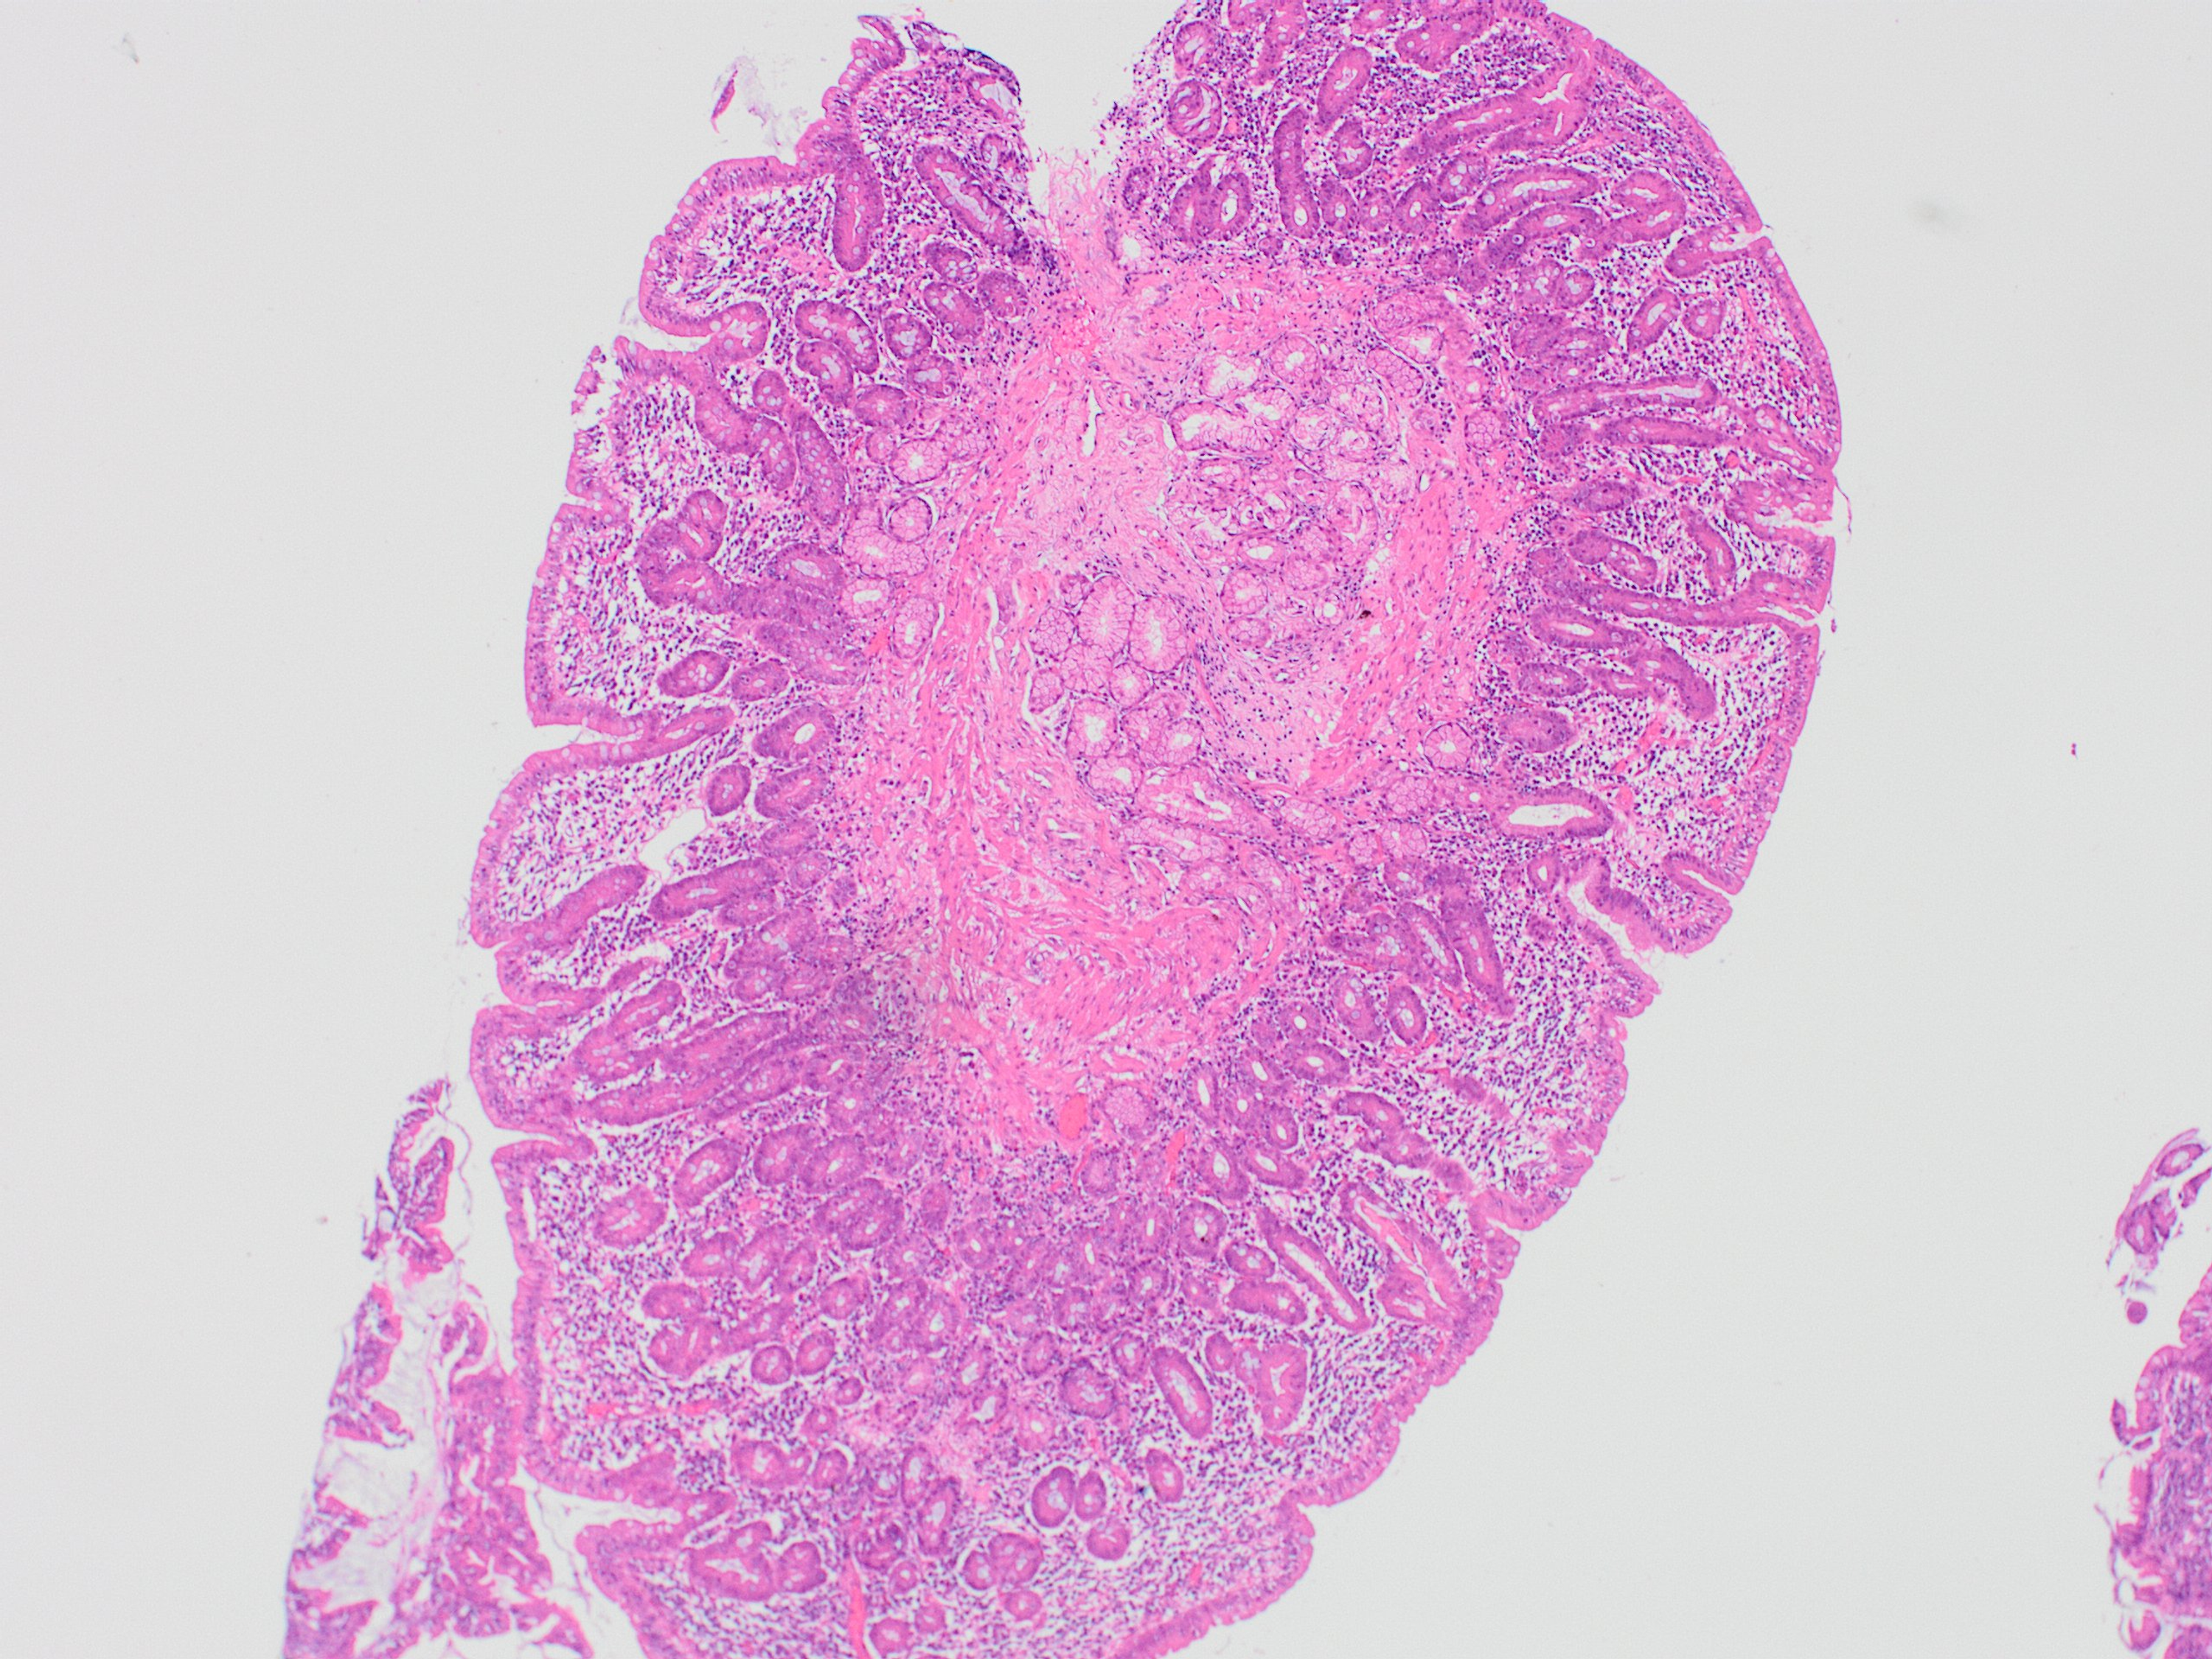

Following the results of the abdominal and pelvic CT, an exploratory laparotomy was performed and a wedge biopsy of the ileal and right colonic wall was sent for histopathological analysis. Pathology subsequently revealed a florid acute serositis with the marked expansion of the subserosal fatty tissue with a hypereosinophilic cell population identified in the right colonic and terminal ileum mucosa and lamina propria (Figures 2-5). There was no evidence of any microorganism, vasculitis, or malignancy including lymphoma.

Biopsy revealed the lower esophageal squamous mucosa to have mild features of reflux with normal mucosa in all other sections and no evidence of eosinophilic esophagitis throughout. Gastric biopsy showed mild chronic inflammation in the pylorus, antrum, and fundus with no evidence of significant eosinophilic cell population and no signs of lymphocytic gastritis. Subtotal villous atrophy was identified in the duodenum with increased intraepithelial lymphocytes (Figures 6, 7). No evidence of neoplastic cell infiltrates was identified in any specimens. Moreover, some fragments of the terminal ileum showed reactive type lymphoid cell population, while others showed normal villous outline with no intraepithelial lymphocytes. There appeared to be a mild increase in cellularity in the lamina propria of the left side of the colon. There was no evidence of lymphoproliferative disease, no features to support eosinophilic gastritis, no evidence of mucosal active inflammation, and no evidence of infective or lymphocytic colitis. Regarding the suspicion of infectious pathology, no organism was isolated.